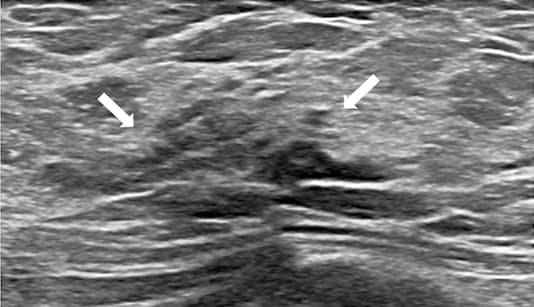

Il s'agit d'une solution intégrée à la suite Olea Sphere® v3.0 qui permet une revue morphologique des différentes séquences IRM et la segmentation automatique des lésions. S'intégrant dans un contexte diagnostique de suivi global, elle assure une optimisation de la prise en charge des patientes, notamment par la mise en œuvre du compte rendu de façon didactique et ergonomique, en lien avec les recommandations BI-RADS®.